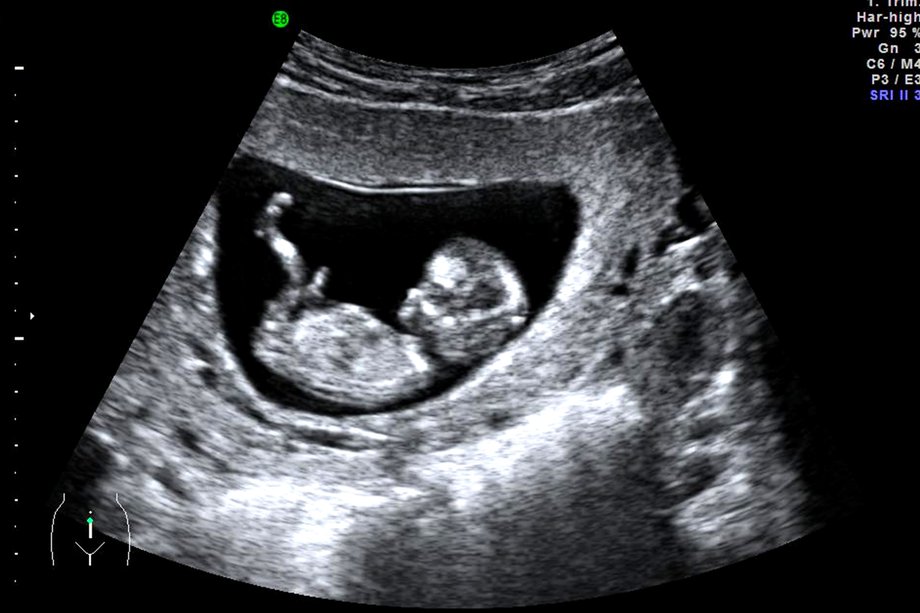

What can be seen on the scan at various stages of early pregnancy?

A pregnancy sac is visible usually at 5 weeks of gestation (calculated from the last menstrual period). A yolk sac becomes visible inside the pregnancy sac as the pregnancy grows and the mean sac diameter reaches 8-10mm. After this a small embryo becomes apparent at about 6 weeks. When the embryo becomes 4mm (6weeks and 2 days), the fetal heart should be visible. By 8 weeks the embryo is readily seen on abdominal scan. Fetal limb buds are seen at 9-10 weeks with body movements.